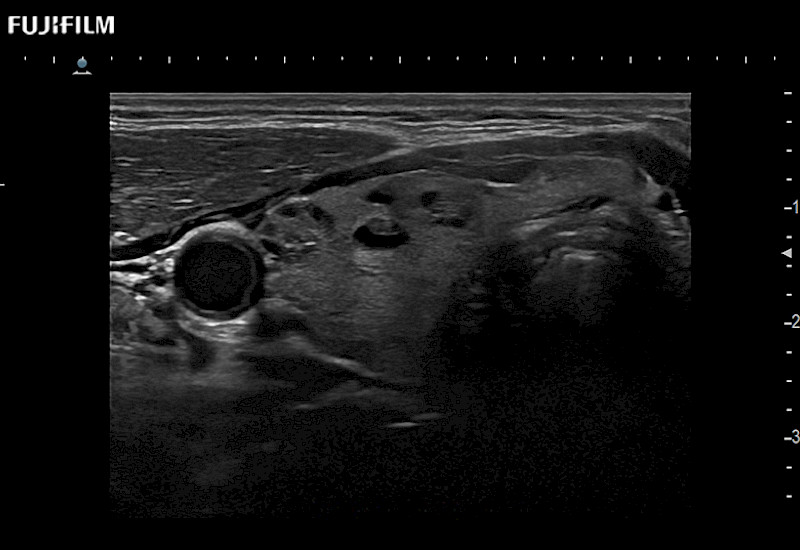

The ARIETTA 750 incorporates all of the proven technologies and functions that medical professionals have come to expect from Fujifilm Healthcare.

ARIETTA 750 is the definitive diagnostic ultrasound solution for any clinical setting - Private Office, Imaging Center, or Hospital. The ARIETTA platform provides the ultimate in clinical performance with its state-of-the-art features and large user-friendly display.

The ARIETTA 650 DI combines trusted Fujifilm Healthcare technologies and features tailored for surgical oncology.

Designed to meet the demands of surgeons, the ARIETTA 650 DI offers precise guidance. Its advanced capabilities and large, intuitive display offer accurate and efficient care in operating rooms and specialized surgical settings.